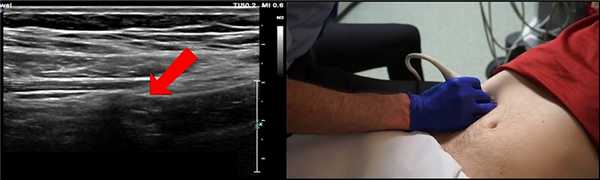

Мы нашили небольшую трубчатую структуру. Это и есть аппендикс

Полезный анатомический ориентир - поясничная мышца. Аппендикс часто можно увидеть над поясничной мышцей